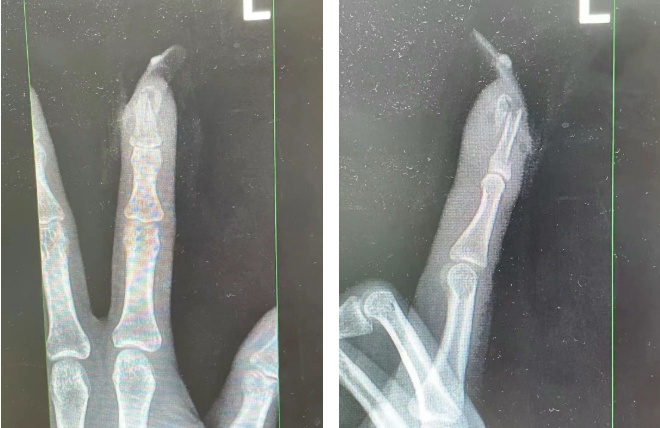

王女士受伤手指的X光影像。图源:杭州市临平区中西医结合医院

经检查

王女士指甲断裂,部分甲床外露

医生表示如果没有美甲

伤害不会这么严重